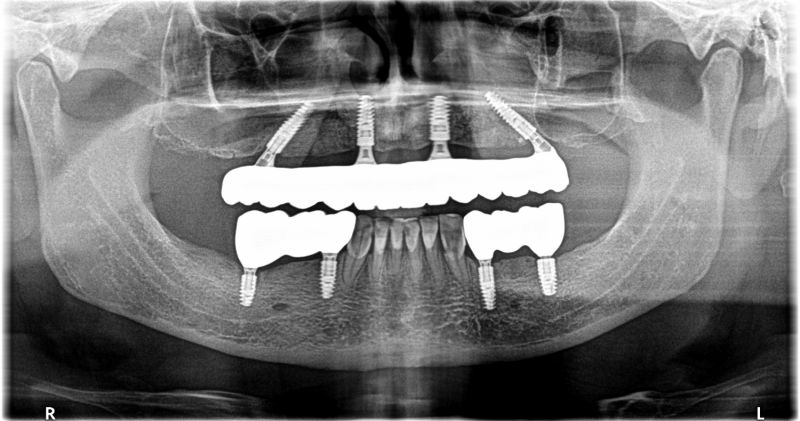

Wykonana praca protetyczna:

- most pełnołukowy na czterech implantach

- mosty pełnoceramiczne na implantach w łuku dolnym

- odbudowa flow-injection na zębach przednich dolnych

Praca wykonana przez: dr n. med. Michała Kubiszyna, lek. dent. Annę Andrzejewicz-Melaniuk

Leczenie zachowawcze: Lek. dent. Paweł Kruk